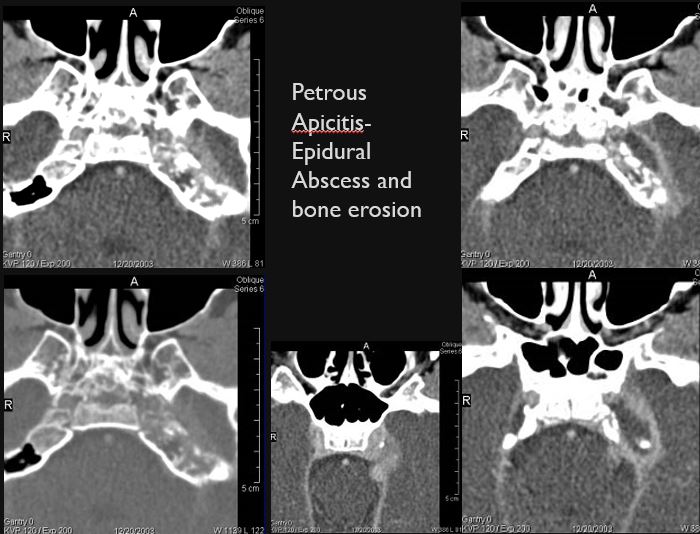

Petrous apicitis associated with middle ear and mastoid disease.

There are dural reactive changes or a subperiosteal/epidural abscess along the sigmoid plate of the mastoid displacing the adjacent sigmoid sinus. [Yes/No]

There is dural reactive change, subperiosteal, epidural or subdural abscess along the roof of the mastoid or middle ear or the superior and posterior (intracranial) surfaces of the petrous portion of the temporal bone. [Yes/No]

There is a subperiosteal, subdural or epidural abscess along the floor of the middle cranial fossa or along the inner (intracranial) surfaces of the petrous portion of the temporal bone or tentorium or falx cerebri. [Yes/No]